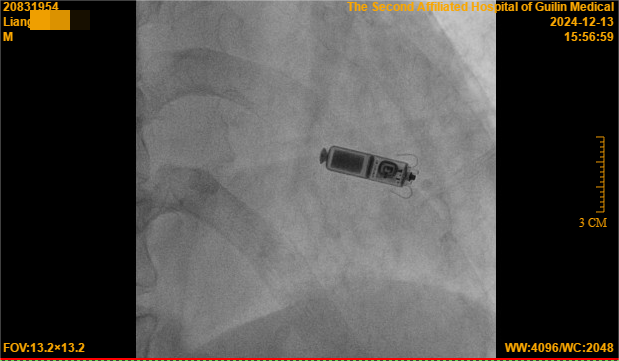

其次无导线起搏器体积小巧,重量轻,直接放置于心腔,患者日常生活中基本感受不到起搏器的存在。这对于梁大爷这样的老年人来说,无疑是一个巨大的福音。他不再需要担心导线移位或断裂的问题,可以自由地进行日常活动,包括洗浴、游泳等,大大提高了生活质量。

12月13日,心血管内科二病区团队通过局部麻醉方式为梁大爷进行了无导线起搏器的植入手术,用时仅45分钟,手术体验良好,几乎无痛感,让怕痛的梁大爷啧啧称赞,起搏器头端的“抓捕器”(电极)精准定位,一次性抓捕到合适的心肌,测试各项起搏参数均非常理想,术后仅有一个小穿刺口,局部加压止血即可。

是一种没有导线的起搏器,它将脉冲发生器与起搏电极合为一体,以“微缩胶囊”的形式直接将起搏器植入患者心腔内部。体积小巧,重量极轻,通常只有约2克,体积约为传统起搏器的十分之一,就像一粒胶囊大小。